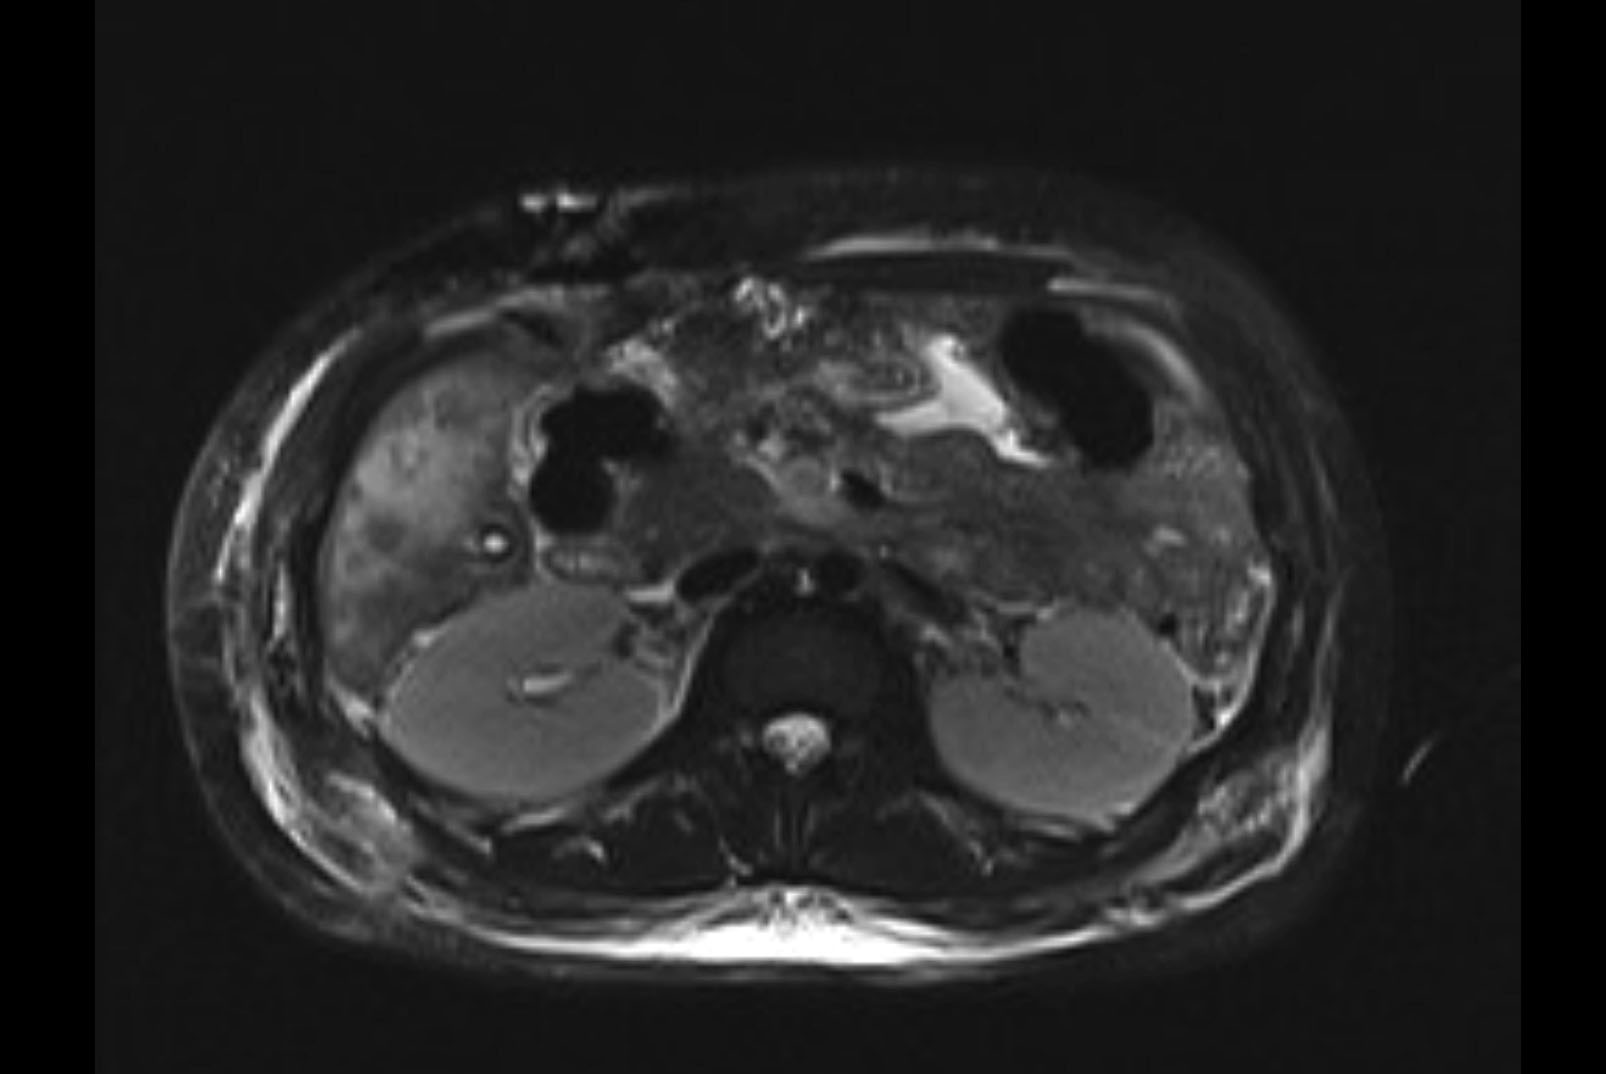

Imaging Analysis

Look through the patient's CT scan to identify any areas of concern for the necessary procedure.

MRI T1

Based on initial findings, which issue(s) would you be most concerned about?